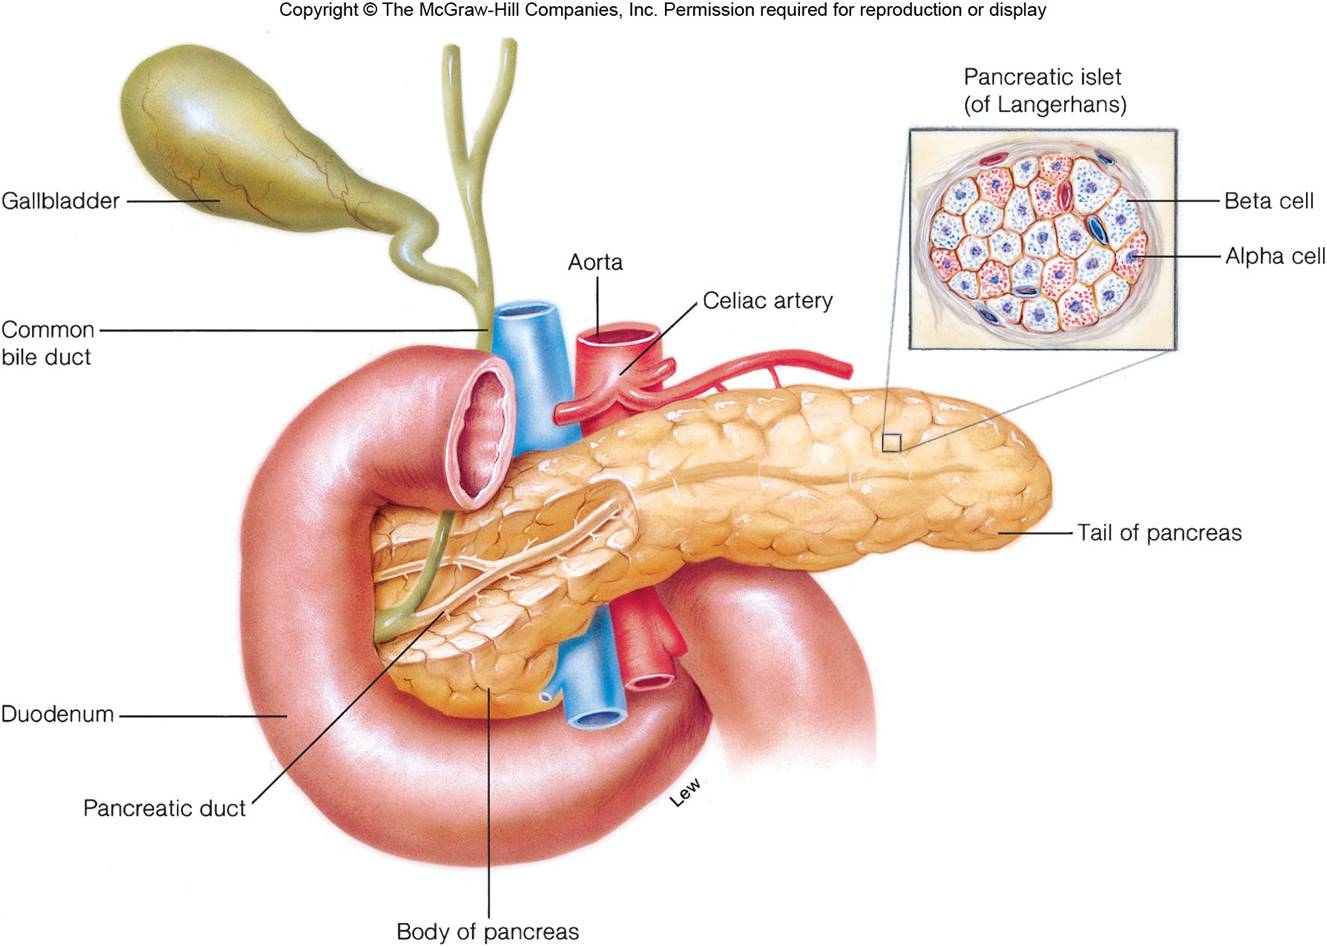

УЗИ диагностика кольцевидной поджелудочной железы: что важно знать